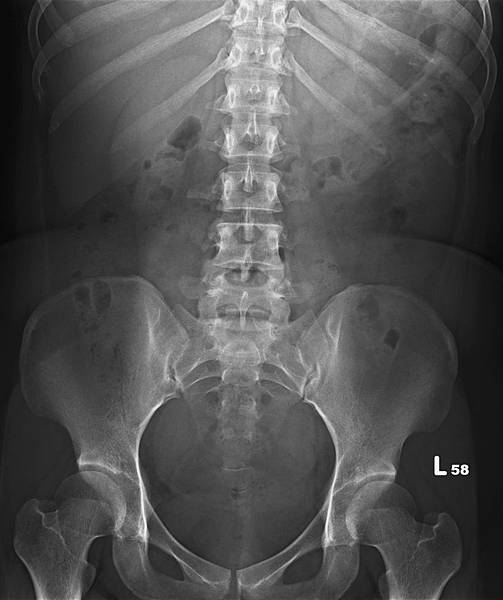

類似的病例很多,下面是上週門診時的胃酸逆流病例,KUB如下:

72歲女性,乙狀結腸(黃箭頭)充滿糞便,但她會告訴你,她每天都有解便。如上圖所示,這樣的病例,病人直腸(藍箭頭)糞便清得很乾淨。